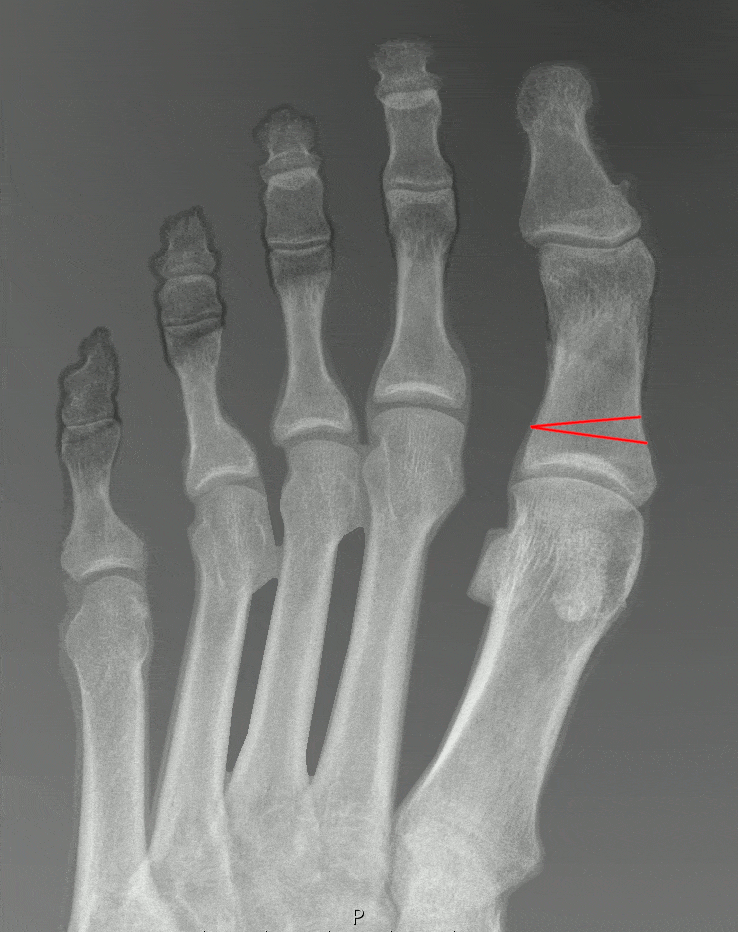

Мы уже обсуждали в прошлом посте, что "шишка" - это не просто костный нарост, а изменение положения костей стопы, что хорошо видно на рентгене:

Пример рентгенограмм стопы в прямой проекции до (слева) и после (справа) остеотомий scarf и Akin